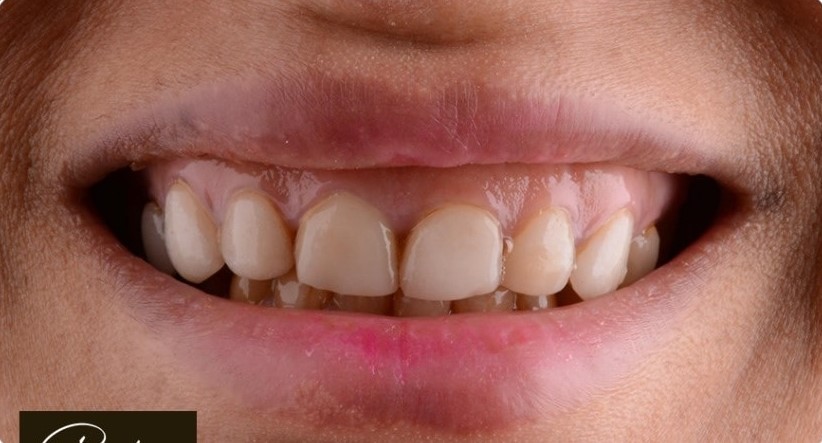

د. حنان ابو الحسن ، مؤسسة Lavender Aesthetic Clinics، هي طبيبة أسنان متخصصة في تركيبات الاسنان ,زراعة الاسنان , حشو عصب ,حشو تجميلي

تميزت برؤيتها اللي بتركز على الجمع بين العلاج الدقيق واللمسة التجميلية، عشان تقدم للمرضى تجربة علاجية مختلفة تجمع بين الصحة، الراحة، والجمال.